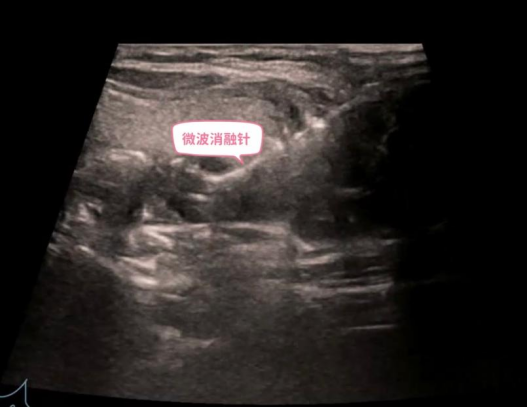

甲状腺和甲状旁腺微波消融治疗是国内近年来逐步开展并推广的一种新型微创治疗技术。在超声的精准引导下,通过一根消融针产生局部高温,以杀死靶细胞,达到灭活病灶或肿瘤的效果。

针对病灶紧贴喉返神经的难题,孙德胜带领团队首先用上了创新的 “水隔离”技术,技术通过细针在目标病灶与喉返神经等关键组织之间,注入生理盐水,人为地创造出一个安全的“隔离带”,为手术上了“第一道保险”。

随后,在超声的实时、高清引导下,微波消融电极化身为精准的“导弹”,沿着安全路径直达已成为“水中孤岛”的增生腺体。启动消融,热能精准释放。整个核心消融过程仅历时42秒,从穿刺到完成,总手术时间约20分钟。

手术后即刻进行的超声造影证实,异常增生的甲状旁腺被成功、完全灭活。整台手术实现 “零出血”。术后监测也证实,患者临床症状便得到显著改善,血清甲状旁腺激素(PTH)水平有效下降,无声音嘶哑,喉返神经功能完好无损。